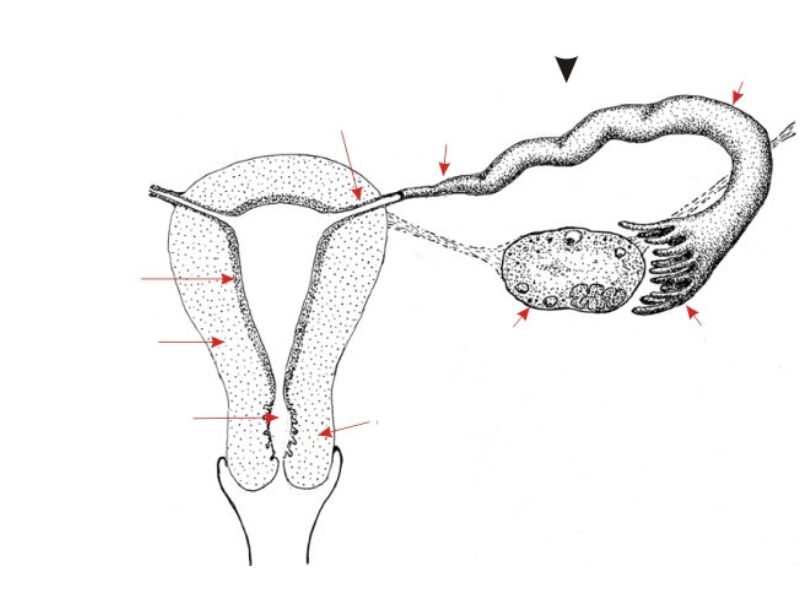

Tuba uterina

Slide 97

Also:

OviductFallopian tube

Uterine tube

Tuba uterina

- Muscular tube

- Most frequent site of fertilization

- Conveys zygote to uterus

- Four regions

- Three layers

Four regions

- Infundibulum

- Ampulla

- Usual site of fertilization

- Isthmus

- Pars interstitialis

- Passes through wall of uterus

Three layers

- Mucosa

- Muscular layer

- Serosa